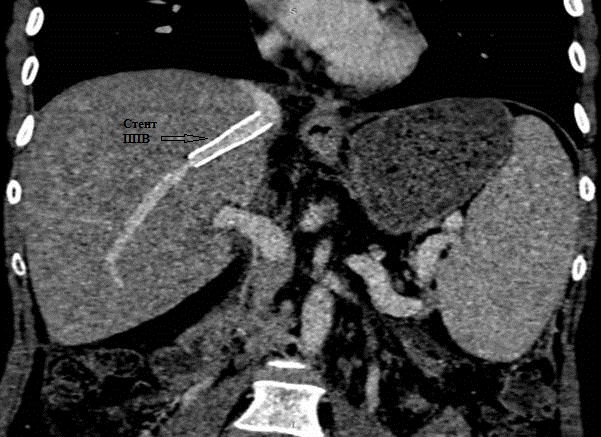

17. Рис. 9а Стеноз ППВ, гипертрофированным трансплантатом | |

18. Рис.9б Состояние после стентирования ППВ | |